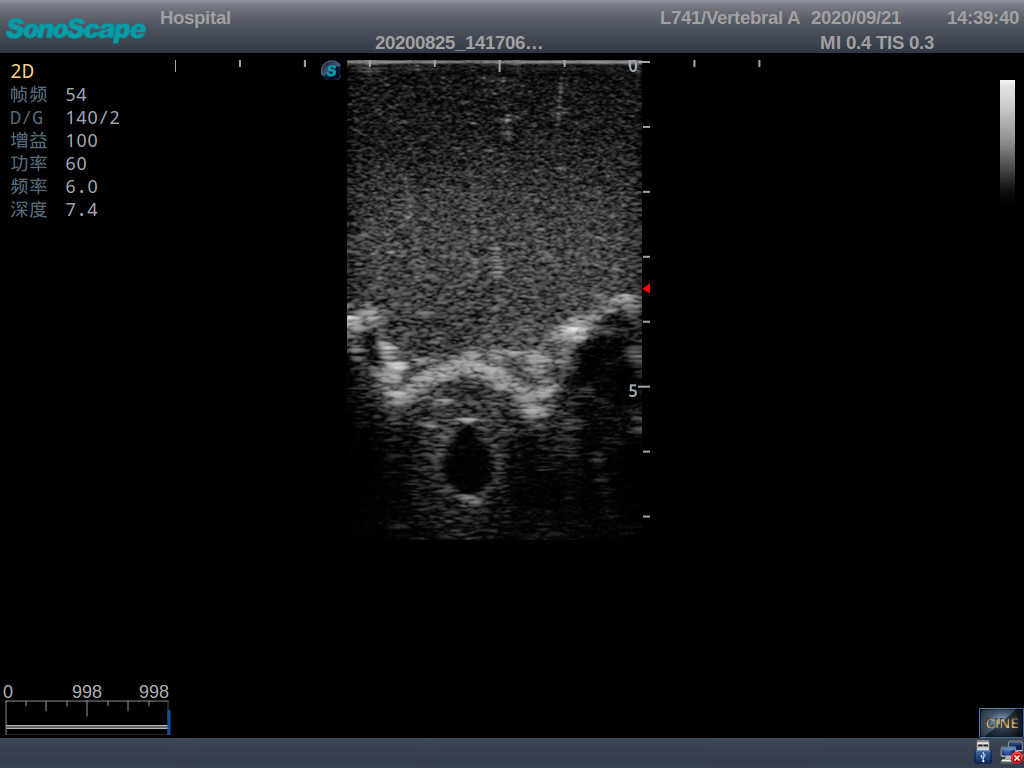

This model is an ideal choice for ultrasound-guided adult lumbar puncture training with true-to-life skin feel and touch, accurate anatomical structures as well as real clinical ultrasound images. Realistic resistance to needle tips and correct landmarks provide excellent hands-on experience.

2)  Real clinical ultrasound images

1)   Ultrasound-guided lumbar puncture practice